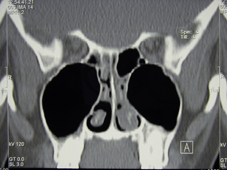

Tietokonetomografiassa on tapahtunut huomattavaa teknistä kehitystä. Monileike-TT (MDCT) on nopea toteuttaa. Aikaa kuvaukseen kuluu vain pari minuuttia. Kuvaus tehdään tavallisesti aksiaalisuunnassa ja muodostetaan sitten laskennallisesti koronaarirekonstruktiot ja tarvittaessa sagittaalirekonstruktiotkin. Tavallisen kuvauksen sädeannos on 60 mAs. Nyt uusissa matala-annos laitteissa (LDCT) sädeannos on saatu pudotettua kuudesosaan ja se vastaa tavallista NSO-rtg:a. Tietokonetomografia mahdollistaa rekonstruktiokuvat. Sitä voidaan käyttää leikkausnavigointilaitteiston kanssa. Nopeat laitteet mahdollistavat angiografiat esim. tuumoriselvittelyissä. LDCT tulee syrjäyttämään natiivikuvat.

Uusi innovaatio on myös mikro-TT, jonka ongelmana toistaiseksi on pieni kartiomainen kuvantamisala. Laitteisto on pieni ja mahtuu jopa vastaanottotilaan. Kuvien resoluutio on erinomainen. Sivuonteloiden selvittelyssä mikro-TT soveltuu toistaiseksi erityisesti hammasperäisen sivuontelotulehduksen tutkimuksiin. Odotettavissa on myös käyttöä korvan kuvantamisessa.